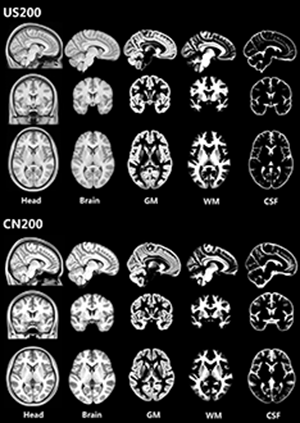

Caucasian and Chinese Brain templates [US200 CN200]

Caucasian and Chinese Brain templates [US200 CN200] Images

1 Images available.

Description: